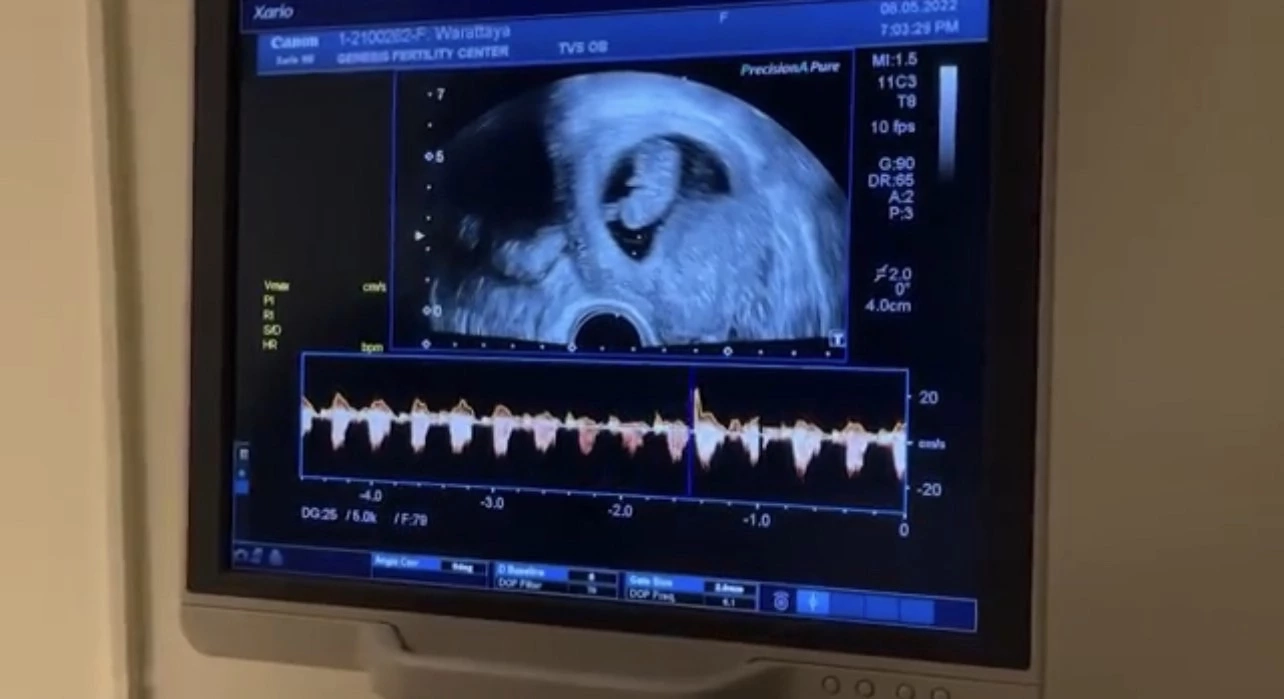

พุฒ : แล้วก็มีอีกหนึ่งครั้งที่น้ำตาซึม ปลื้มปิติดีใจมากๆเลย คือ ลูกคนแรกของเราตอนที่เราไปอัลตร้าซาวด์ดูความเจริญเติบโตของ PJ น้อยเป็นอย่างไรบ้างเราได้ยินเสียงหัวใจของเขาตื่นได้เห็นแสงกระพริบๆแบบหัวใจดวงน้อยๆเล็กๆมาก บอกเลยวันนั้นที่ยืนดูเขิน น้ำตาก็จะไหล

จุ๋ย : จริงๆต้องบอกเลยว่าเราโชคดีที่เราได้ยินเสียงหัวใจเร็วมากๆ